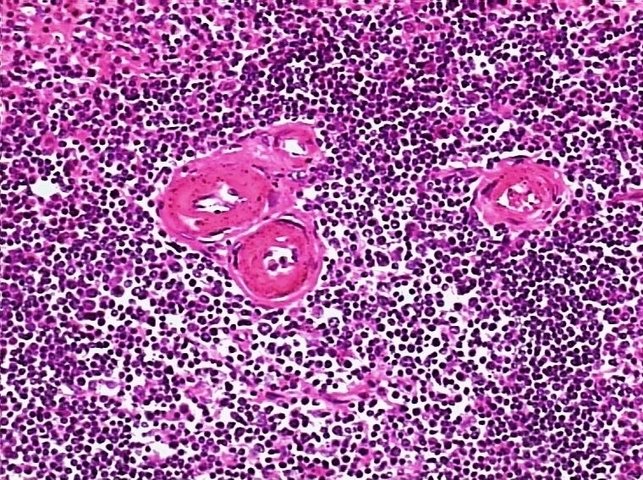

生物病理显微镜切片脾透明变性标本白底微距摄影